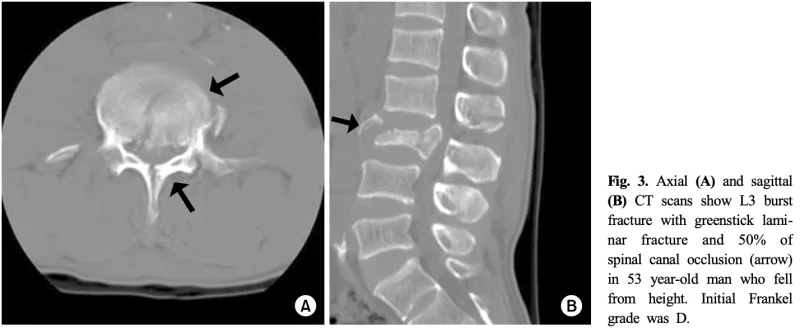

本日撮影したX線写真では, 椎体の高さが29 mmから24 mmと5 mmも短縮しており, また, 椎体後壁にも骨折が及んでいて, 破裂骨折と診断し, CTをオーダーしました.

骨片が脊柱管内に突出して, 脊柱管が狭くなっています.

また, 椎体後方の椎弓の骨折を合併しています.

その結果, 脊柱管内に骨片が突出していました.